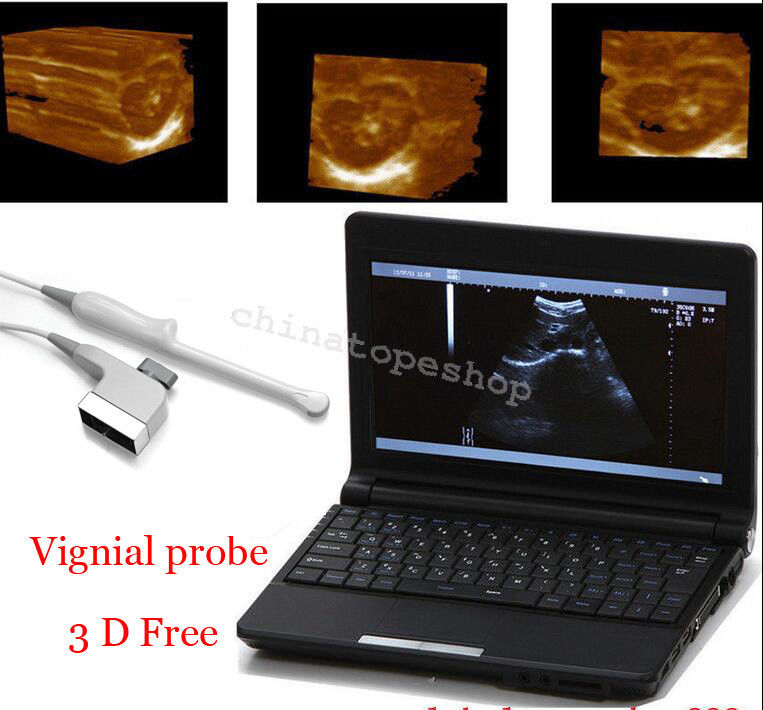

The Laptop Ultrasound Scanner combines cutting-edge technology with portability to enhance your medical practice. This device allows for high-quality ultrasound imaging, ensuring that healthcare professionals can provide accurate diagnoses. Additionally, it features a Transvaginal probe that delivers detailed views of internal structures, making it indispensable for gynecological examinations. Because of its sophisticated design, you can easily operate it in various clinical settings.

High-Quality Imaging Meets Practical Functionality

With the inclusion of a 3D workstation, the Laptop Ultrasound Scanner offers enhanced imaging capabilities that allow healthcare professionals to view detailed 3D images. This functionality improves diagnostic accuracy and helps in monitoring various conditions over time. Additionally, the software included enables efficient storage and easy retrieval of images, supporting medical professionals in their evaluations. Hence, this scanner not only provides high-quality imaging but also practical functionalities that are essential for modern medical practices.